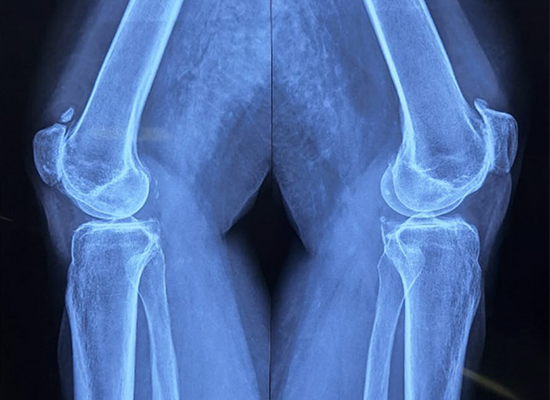

Preoperative Imaging

Preoperative X-ray - Anterior View

Examination revealed knee deformity